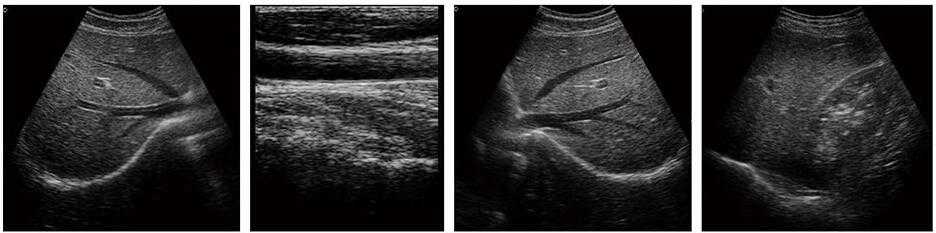

DW-370黑白B超機

3、適用于常規腹部、子宮附件、淺表組織等臨床檢查

1、掃描方式:凸陣、線陣、微凸

5、用途說明:主要應用于腹部、泌尿科、婦產科、血管等